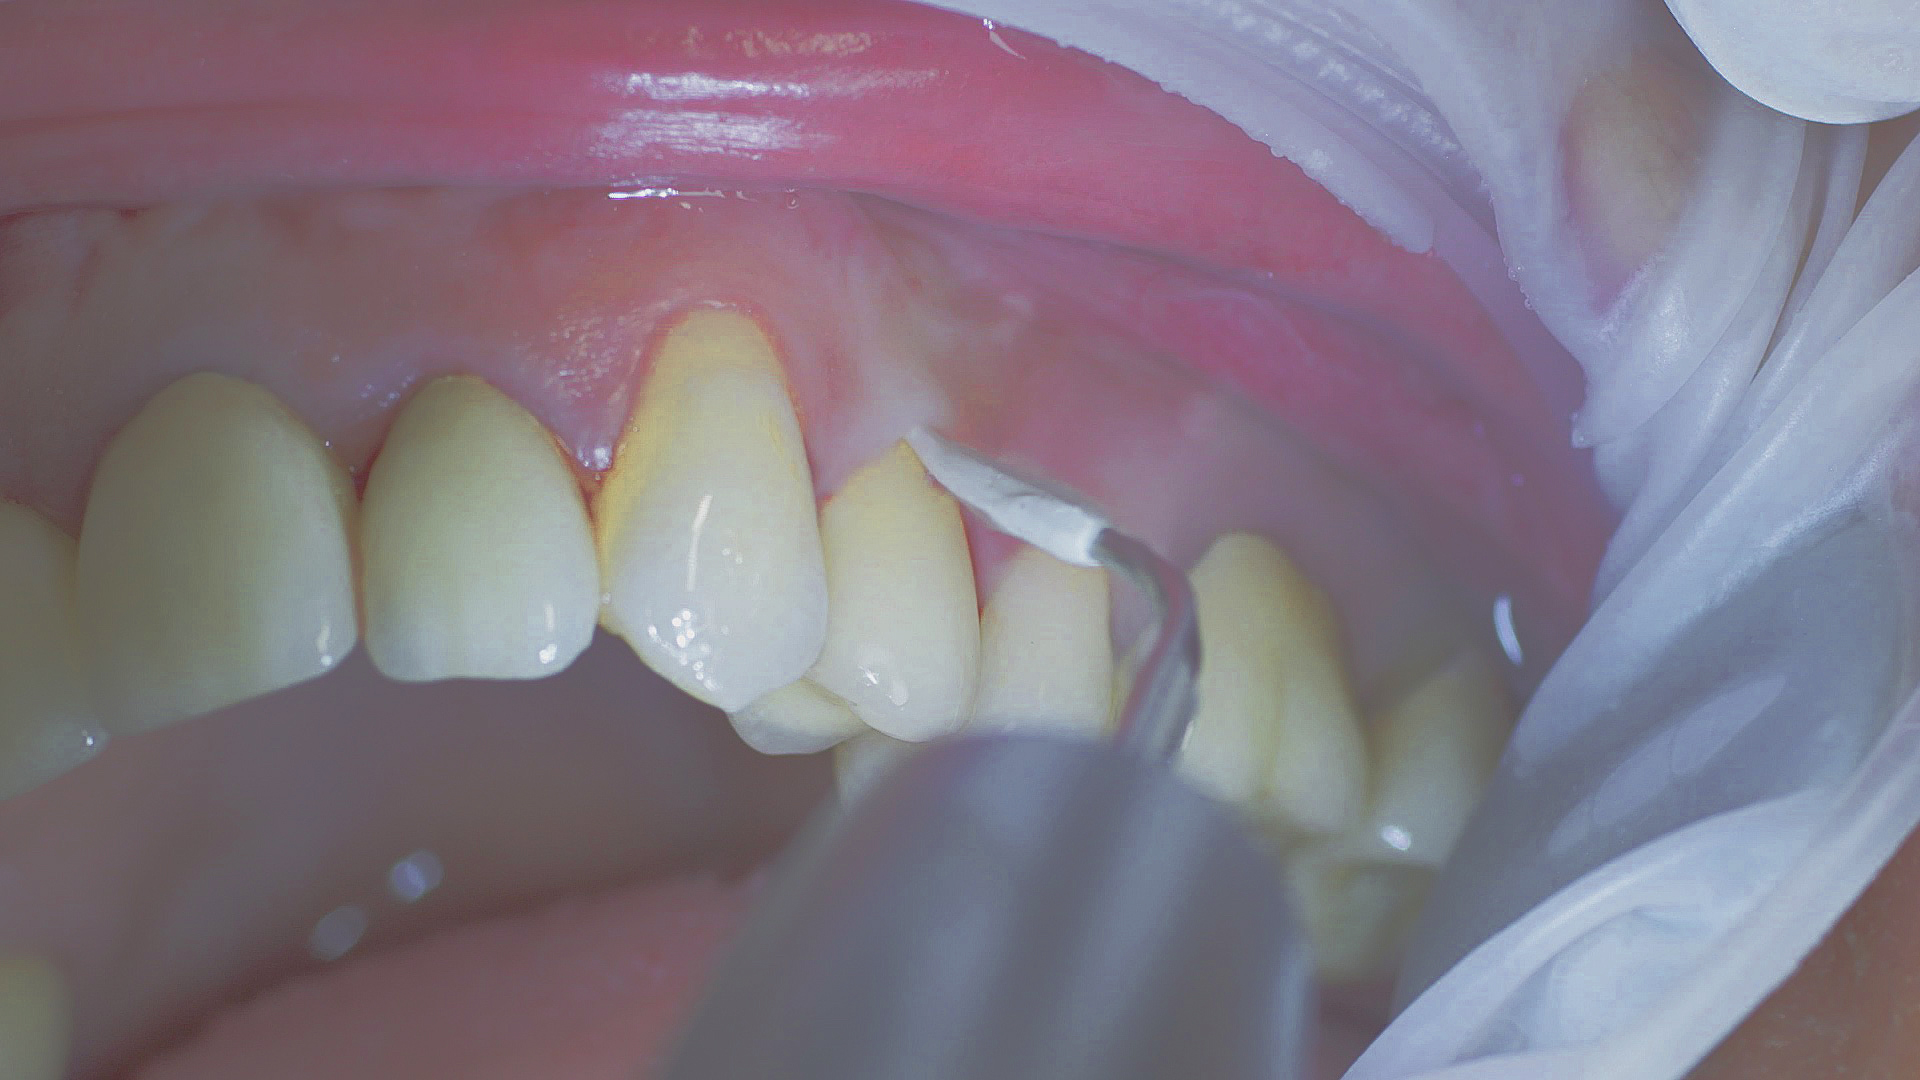

Where necessary, initial periodontal treatment is carried out. First, professional tooth cleaning establishes healthy gingival conditions. In this procedure, calculus (Fig. 1) and biofilm (Fig. 2) are removed as far as the gingival sulcus. In combination with careful instruction on oral hygiene, this gives the patient the basis for long-term freedom from inflammation.15

Rotary cleaning with prophylaxis polishing cups and brushes

Fig. 2: Rotary cleaning with prophylaxis polishing cups and brushes (W&H Proxeo prophylaxis contra-angle handpiece) ensures smooth surfaces on teeth. It enables patients to check biofilm effectively at home.